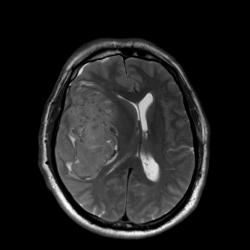

В продолжение темы нарушений мозгового кровообращения публикую случай геморрагического инсульта.

Наличие крови наиболее четко видно на T2* GRE импульсной последовательности.

Наличие крови наиболее четко видно на T2* GRE импульсной последовательности.

magnetom, абсолютно закономерное предположение!

Чисто теоретически сверхострую гематому сложно отличить от опухоли. Давайте разбираться: эритроциты, только что вышедшие за пределы сосуда (артерии), содержат полностью оксигенированный гемоглобин и другие комоненты крови. Оксигемоглобин имеет диамагнитные свойства и будет давать умеренно гипоинтенсивный сигнал при T1 ВИ и слабогиперинтенсивный сигнал на T2 ВИ. Такую же интенсивность МР сигнала могут давать и некоторые опухоли.

Гематому в данном случае с головой выдает периферическая полоска, окружающая образование с гипоинтенсивным (особенно на GRE ИП) МР сигналом. Иначе чем еще ее можно объяснить?

Ув. Андрей! На представленных МР-томограммах при геморрагическом инсульте с большой зоной поражения, где причиной кровоизлияние иногда бывают следующие факторы: разрыв артерио-венозной мальформации, разрыв аневризмы обязательно проведение МР-ангиографии (что очень важно для хирургической тактики ведения пациента), для исключения кровоизлияния в опухоль желательно проведение не только МР-ангиографии, но и введение контрастного вещества при базовом МР-исследовании, что тоже даст дополнительную информацию. Данный случай, что предоставил нам уважаемый Евгений, МР-исследование проводилось на современном высокопольном магните, поэтому МР-ангиография и трактография не занимают много времени, а информацию для врачей лучевой диагностики и нейрохирургов предоставляют очень существенную.